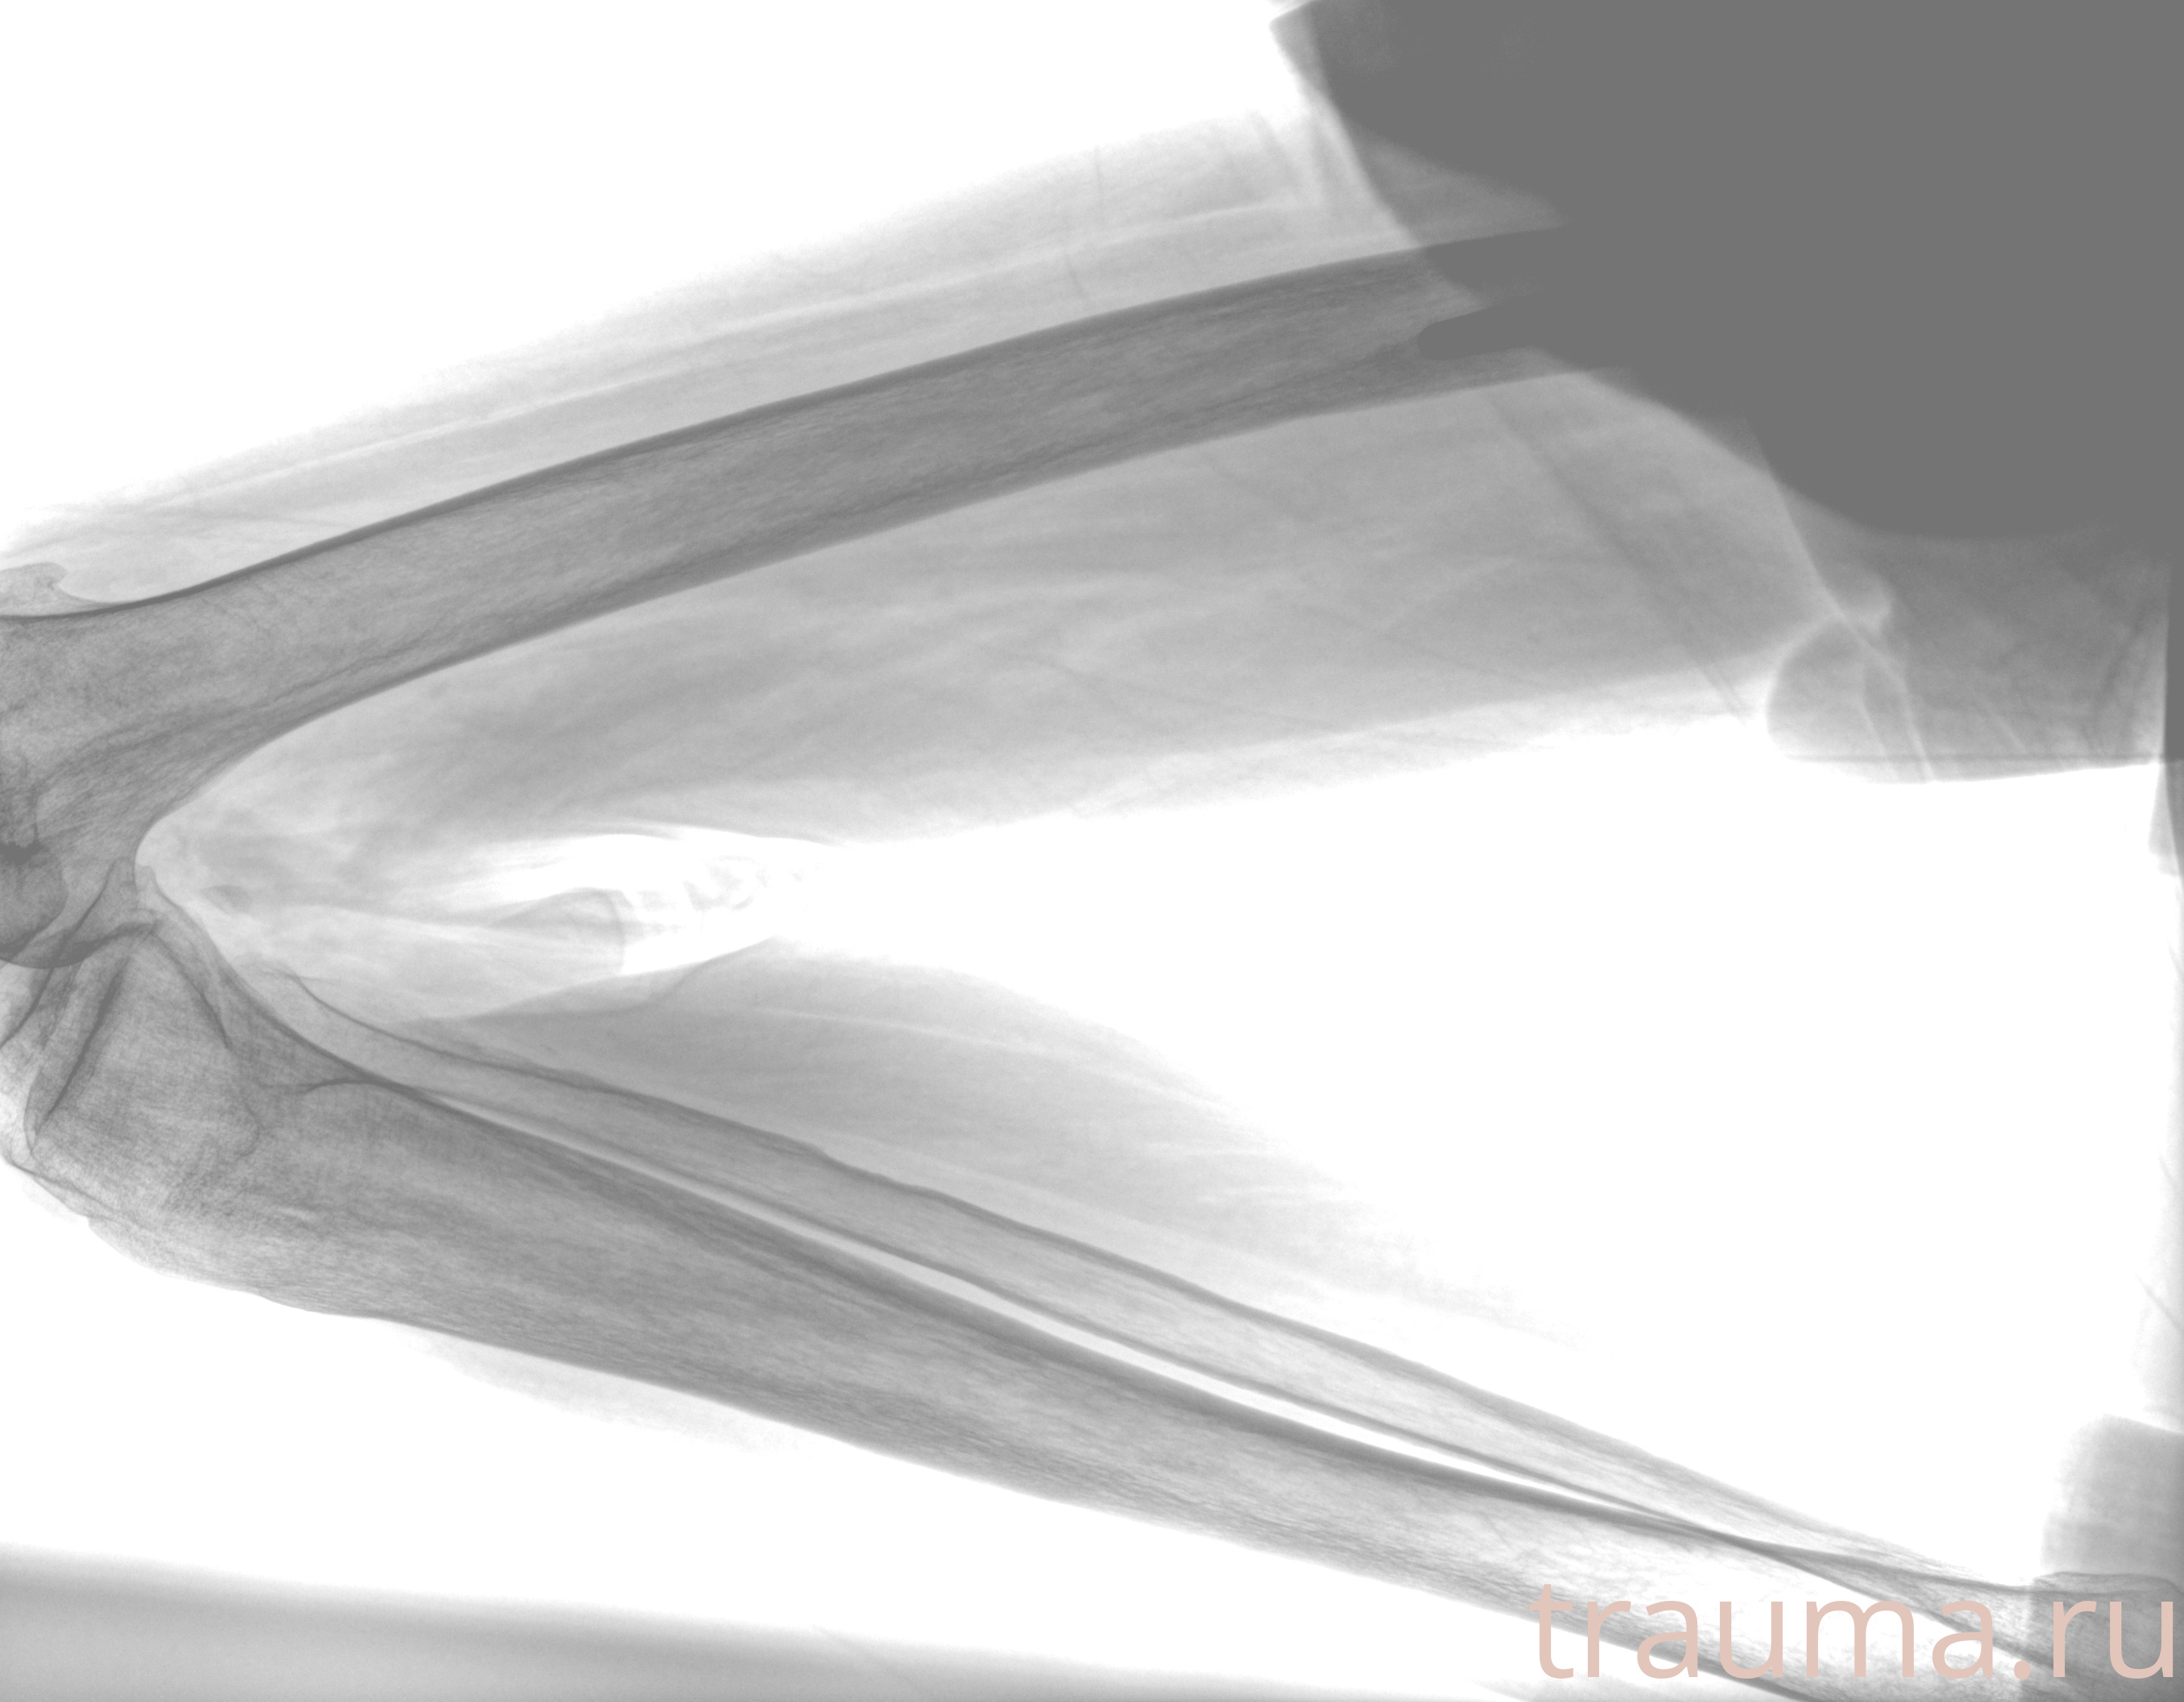

Рентген на дому: по вашему адресу приезжает врач-рентгенолог, травматолог-ортопед с мобильным рентгеновским аппаратом, проводит диагностику травмы или заболевания, делает необходимые рентгенограммы, дает рекомендации по дальнейшему лечению. Получить качественные снимки в домашних условиях возможно благодаря уникальной методике, разработанной МосРентген Центром для института  Склифосовского